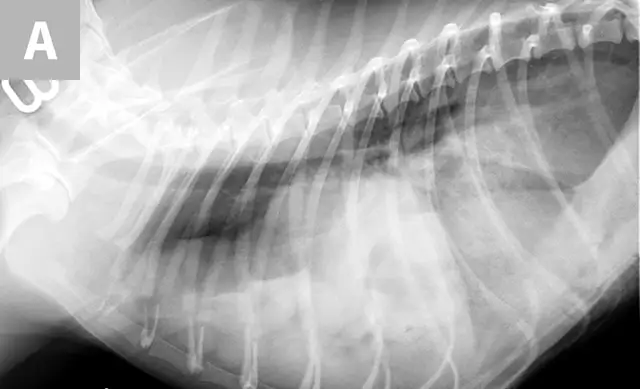

FIGURE 1A

Diaphragmatic hernia involving herniated liver, small intestine, colon, spleen, and mesentery in a 6-year-old spayed domestic shorthair cat.